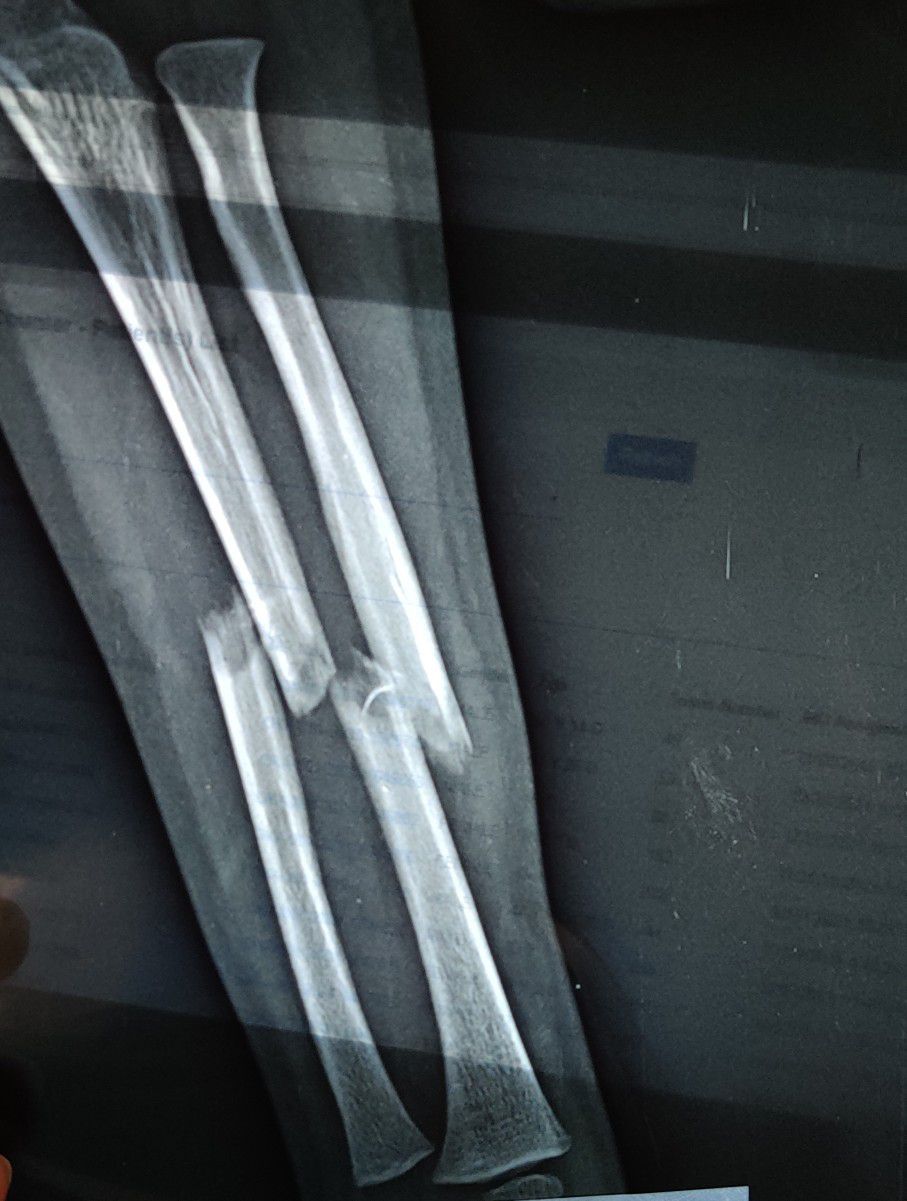

Radius + Ulna Fracture

Fracture

Radius

Ulna